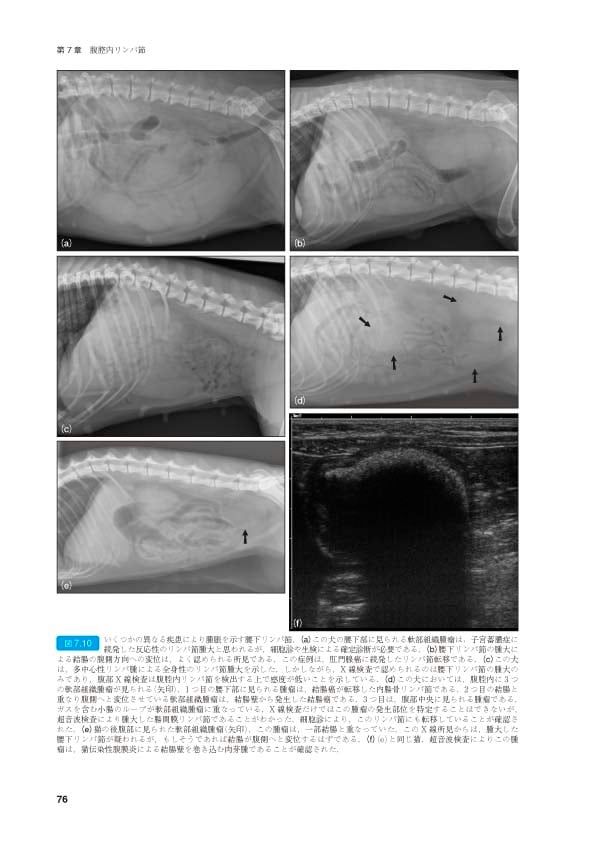

犬と猫の腹部外科に関する詳細なマニュアル。- タイトル: 犬と猫の腹部外科マニュアル- 編集者: John M. Williams and Jacqui D. Niles- シリーズ名: BSAVA マニュアルシリーズ表紙にテープ跡があります。ご覧いただきありがとうございます。